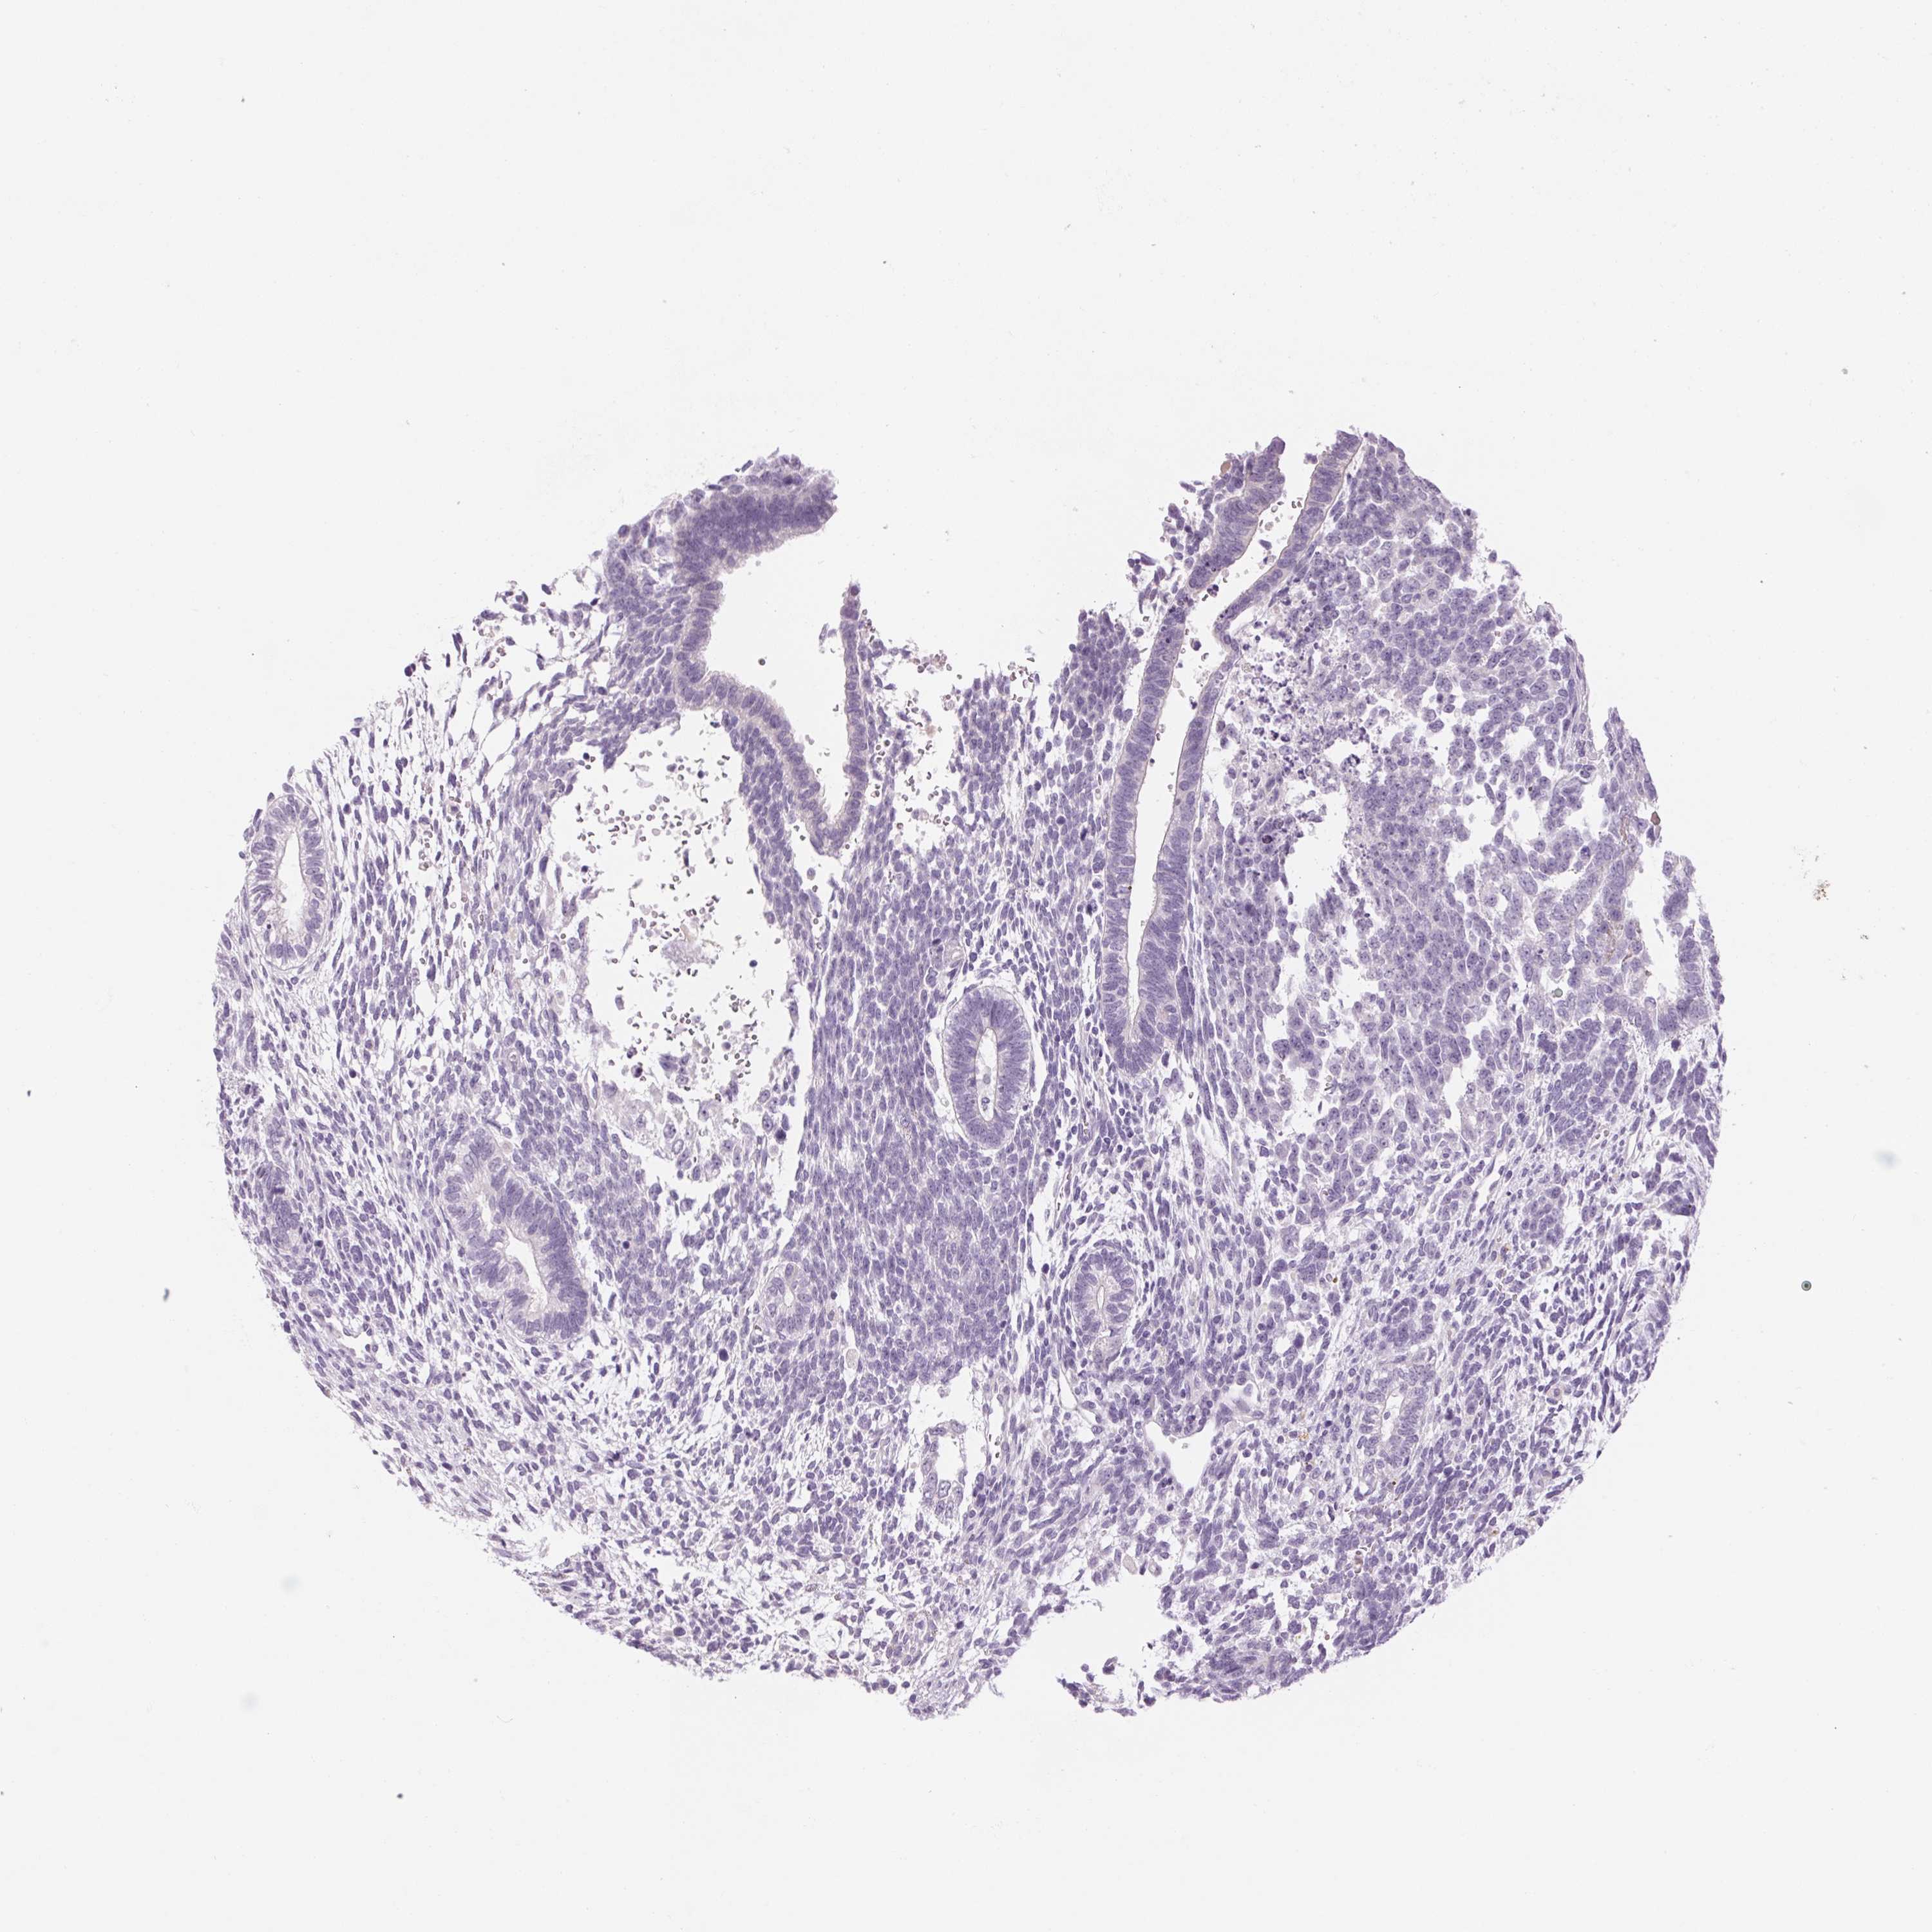

TESTIS CANCER - Protein expressioni

A mouse-over function shows sample information and annotation data. Click on an image to view it in a full screen mode. Samples can be filtered based on level of antibody staining by selecting one or several of the following categories: high, medium, low and not detected. The assay and annotation is described here.

Note that samples used for immunohistochemistry by the Human Protein Atlas do not correspond to samples in the TCGA dataset.

Antibody stainingi

Antibody staining in the annotated cell types in the current human tissue is reported as not detected, low, medium, or high, based on conventional immunohistochemistry profiling in selected tissues. This score is based on the combination of the staining intensity and fraction of stained cells.

Each image is clickable and will lead to virtual microscopy that enables deeper exploration of all samples and also displays staining intensity scores, fraction scores and subcellular localization as well as patient and tissue information for each sample.

Antibody HPA030483

Antibody HPA030485

Seminoma, NOS

Carcinoma, Embryonal, NOS

Teratoma, malignant, NOS